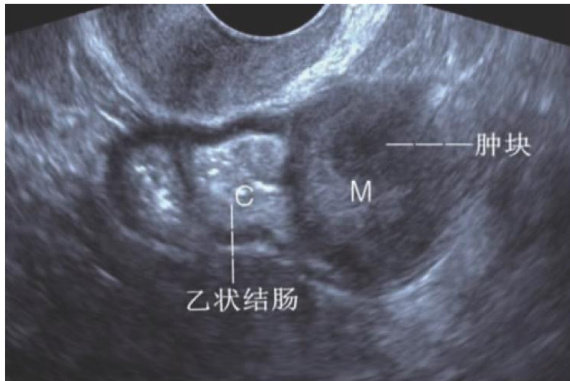

乙状结肠神经鞘瘤超声诊断一例及文献复习

ABSTRACT:Sigmoid colon schwannoma is a rare benign gastrointestinal tumor that is challenging to be diagnosed preoperatively.This paper reported acase of sigmoid colonschwannoma that was preoperatively misdiagnosed as a gastrointestinal stromal tumor on ultrasonography. Intraoperative frozen section analysis identified it as a spindlecell tumor,withdefinitive diagnosis confirmedasgastrointestinal schwannomavia immunohistochemistry.This paper summarizes the similaritiesand diferentiating features of intestinal stromal tumorsand schwannomas on ultrasonographic imaging. By analyzing and discussing previous literature,we aim to enhance the diagnosticand differential diagnosticcapabilitiesof ultrasonographers in preoperativeevaluationof intestinal schwannomas,thereby providing reliable evidence for clinicians in the diagnosis and management of this condition.

神经鞘瘤是来自神经鞘细胞的良性肿瘤,来源于神经外胚层的施万细胞和中胚层的神经内膜,可发生于全身任何有施万细胞的部位,好发于脊髓和脑,多单发,瘤体生长缓慢,病程可达20年以上。(剩余5542字)